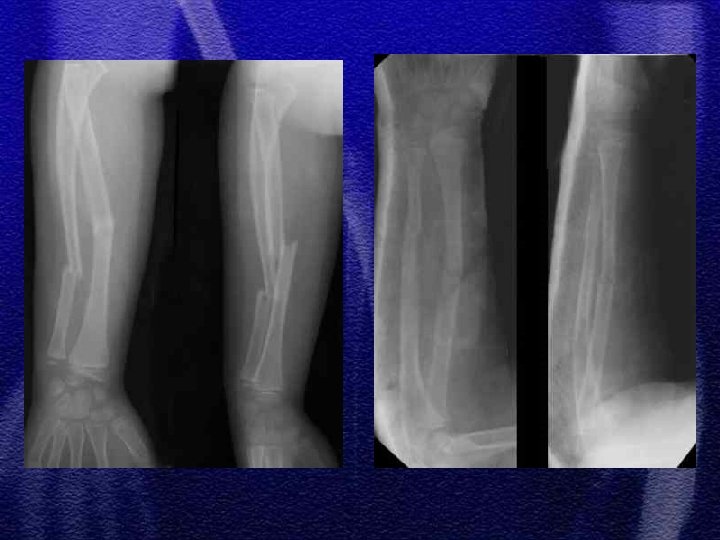

§ Specyficzne - to złamanie typu „zielonej gałązki”, przy złamaniach tego typu okostna nie jest uszkodzona całkowicie, dotyczy to również warstwy korowej § Przy repozycji należy złamać pozostałą warstwę korową, ponieważ zapobiega to wtórnemu przemieszczeniu

§ U dzieci starszych podobnie jak u dorosłych przydatny jest podział dotyczący lokalizacji złamania - określający 3 strefy złamania § W wieku rozwojowym rzadko występuje złamanie typu Galeazzi odmiana dziecięca to złamanie dalszej przynasady kości promieniowej ze złuszczeniem dalszej nasady kości łokciowej

§ Najczęściej repozycja zamknięta § Konieczne kontrole rtg. w 3, 7, 14 dobie z uwagi na możliwość wtórnego przemieszczenia § Leczenie operacyjne - płytki, drut Kirschnera

§ Wyznaczenie jednoznacznego kryterium do zaakceptowania zrostu nieprawidłowego we wstępnej fazie leczenia jest trudne § Przemieszczenie do boku nawet o szerokość trzonu można zaakceptować § Przemieszczenia kątowego >20° nie można akceptować § Przemieszczenia rotacyjne nie podlegają korekcji § Zasadnicze znaczenie ma wiek dziecka